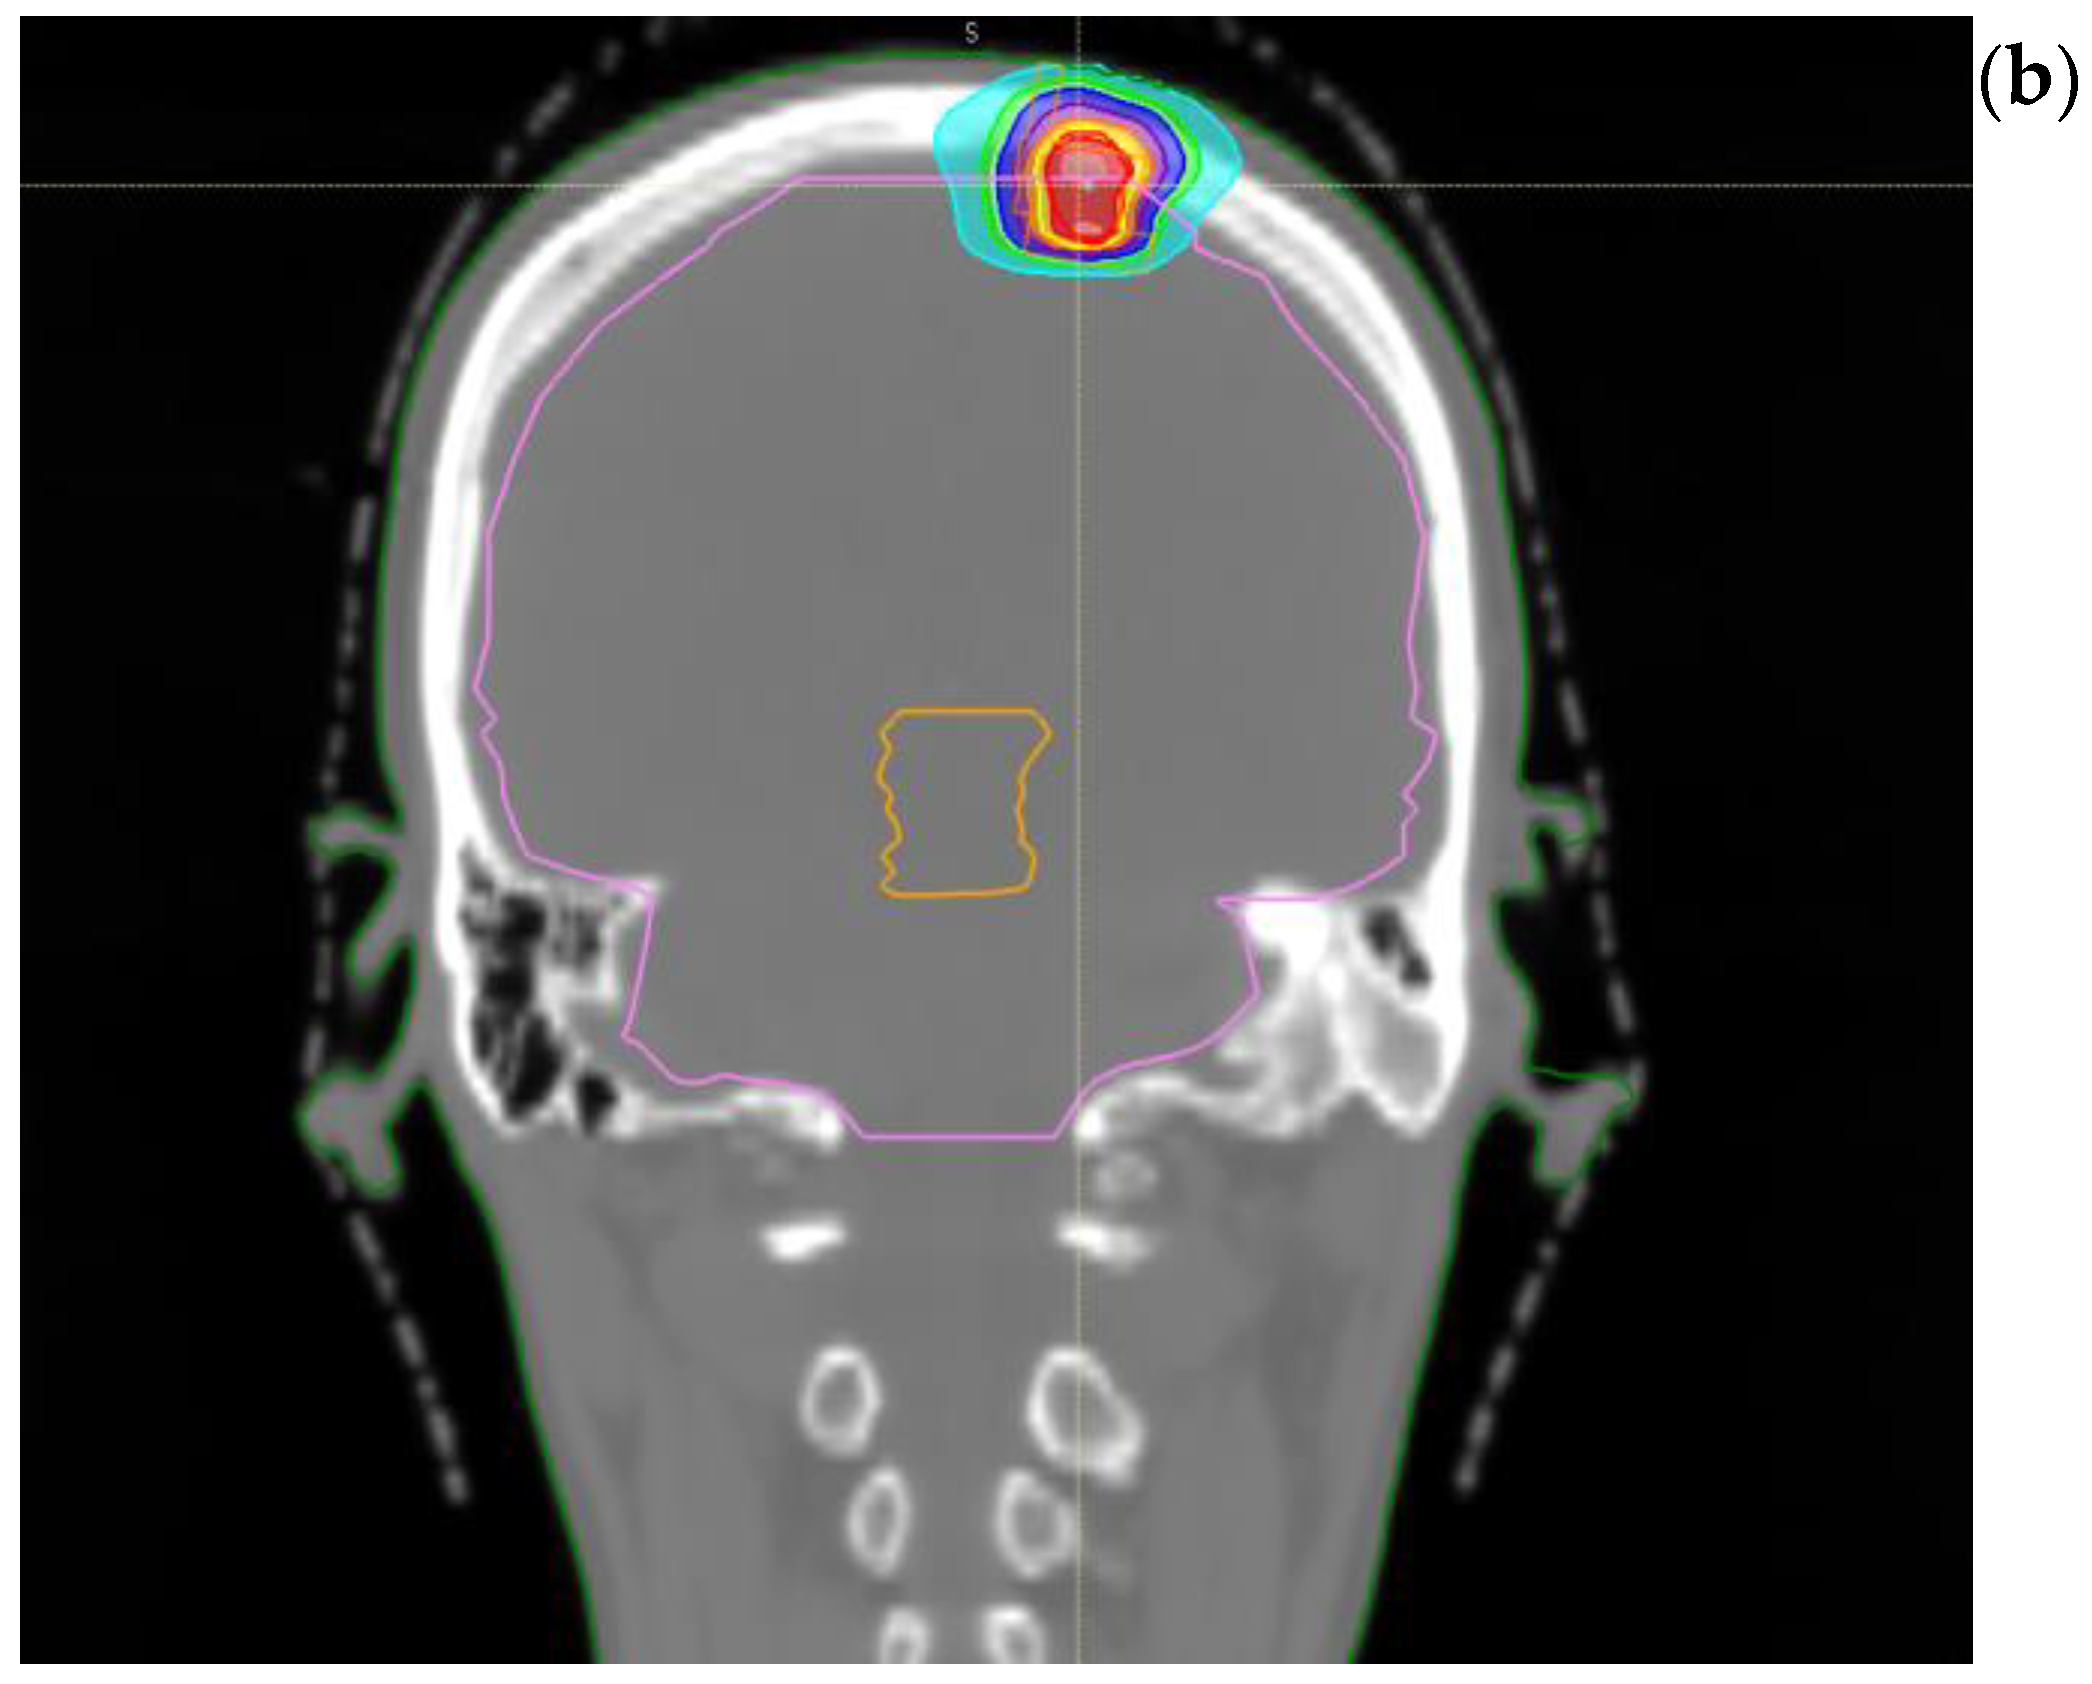

2. Case Presentation